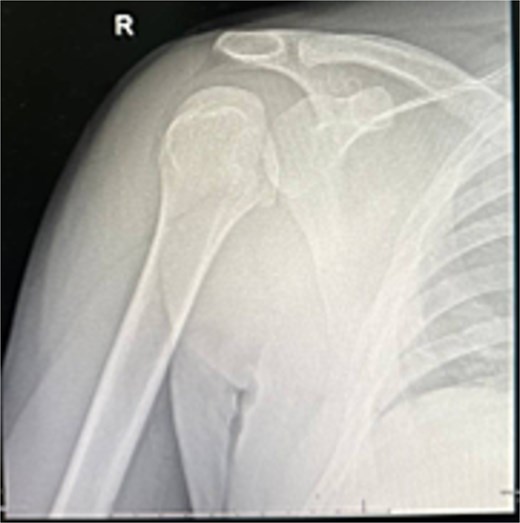

X-rays and CT confirmed missed locked posterior dislocation with healed comminuted fracture and large reverse Hill-Sachs lesion. MRI revealed posterior shoulder dislocation, reverse Hill-Sach’s lesion (Fig. 2) around 2.5 cm in diameter and 1.7 cm in depth, posterior labral tear, and secondary avascular necrosis.